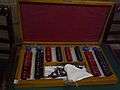

| Refraction box | has lenses of different powers for refraction testing |

Lenses used for refraction testing

A set of lenses used in refraction testing